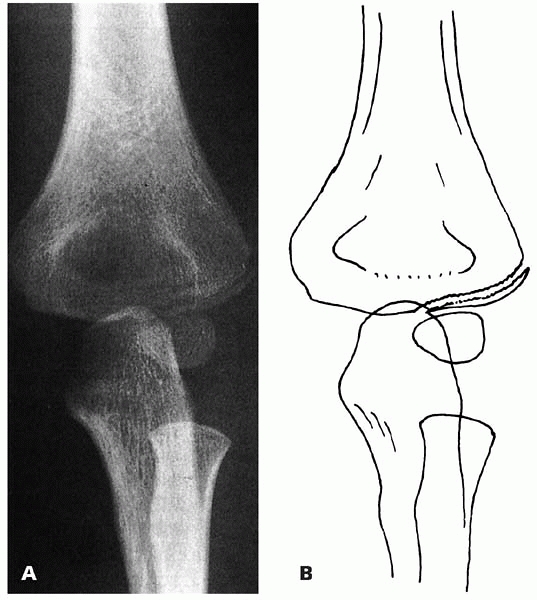

▪ FIGURE 6-3 A:

Type B fracture. Fracture through the lateral humeral condyle with a gap laterally. The fracture can be followed to the epiphyseal cartilage. B: Outline of the radiograph. (Reprinted with permission from Finnbogason T, Karlsson G, Lindberg L, et al. Nondisplaced and minimally displaced fractures of the lateral humeral condyle in children: a prospective radiographic investigation of fracture stability. J Pediatr Orthop. 1995;5(4):422-425.) |

However, when the fracture line extended into the epiphysis, with the

lateral gap greater than the medial gap, 17% (6/35) of fractures

displaced (Fig. 6-3). When the fracture gap at the epiphysis was equal to the lateral gap, 42% (5/12) of fractures displaced (Fig. 6-4).